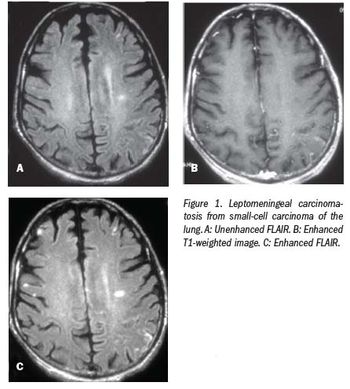

Contrast-enhanced FLAIR is more sensitive than other MRI techniques due to T2 prolongation and T1 shortening.